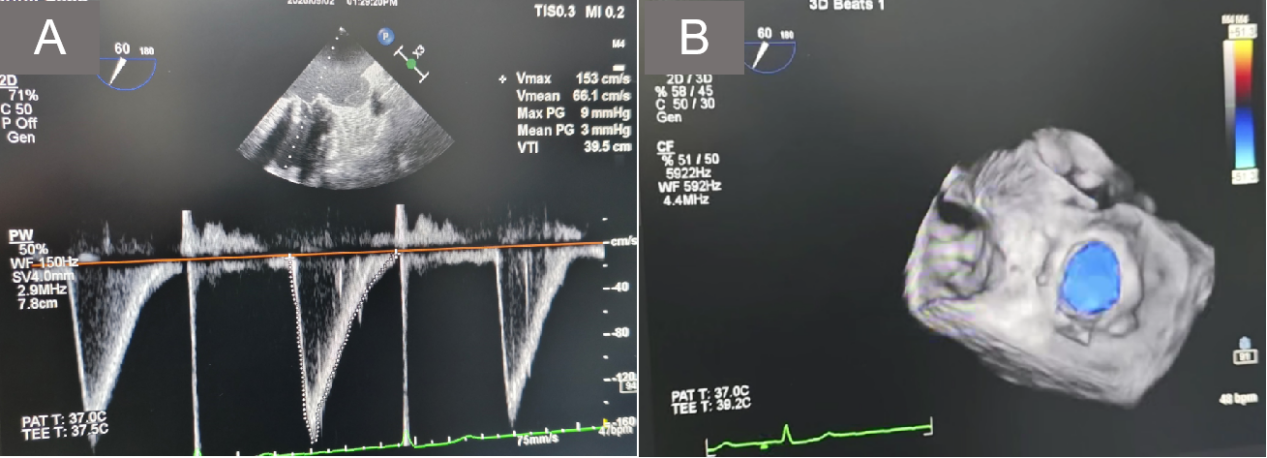

术后心脏彩超所示:A.跨二尖瓣压差3mmHg;B.二尖瓣无返流

手术耗时仅不到 60 分钟,造影显示治疗后二尖瓣无一丝反流,随后的心脏彩超复查显示,新植入的瓣中瓣工作状态良好。

术后三天,陈伯的心衰症状基本缓解,血脑钠肽前体接近正常,复查心脏彩超二尖瓣瓣中瓣工作良好,无狭窄及瓣周漏,左心房、左心室也明显缩小。出院时,陈伯的女儿不禁激动地流泪:“父亲第三次获得新生,是王教授团队精湛医术为她的父亲再造‘心’生命!”